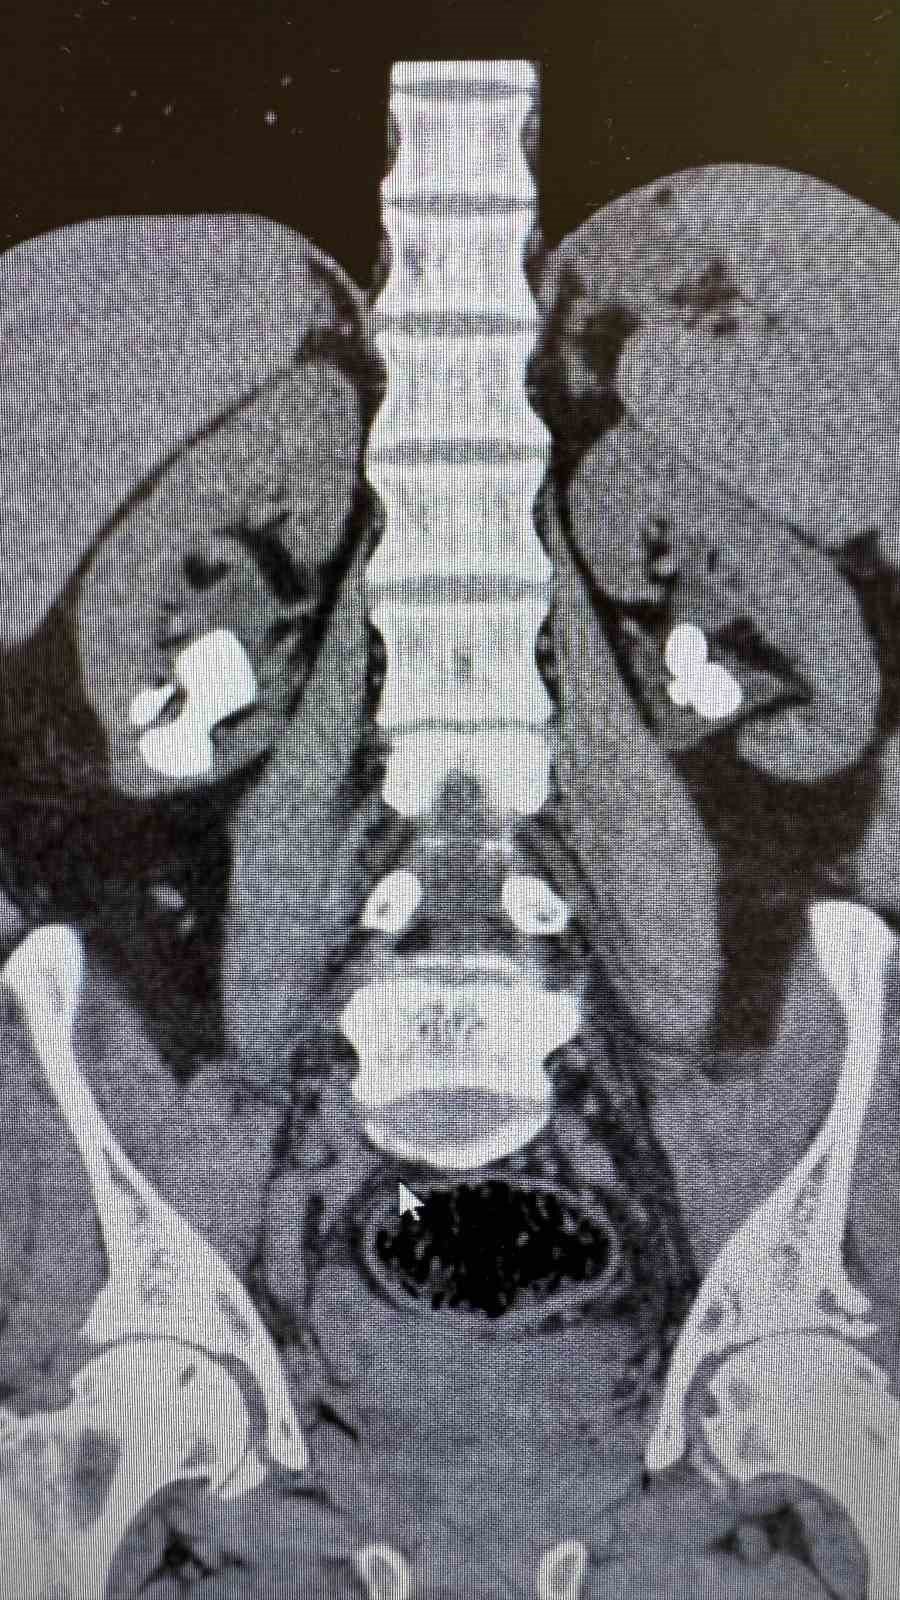

Üroloji Uzmanı Op. Dr. İlker Fatih Şahiner ve ekibince kapalı yöntemle (PNL) yapılan ameliyatlarda hastanın her iki böbreğindeki tekrarlayan sistin taşları temizlendi. Hastanın daha önce 10'un üzerinde böbrek taşı ameliyatı geçirdiği öğrenildi. Mayıs ayında yapılan ilk operasyonla sol böbrekteki taşlar alınırken, geçtiğimiz salı günü gerçekleştirilen ikinci operasyonla sağ böbrekteki taşlar da temizlendi.

Operasyonları gerçekleştiren Üroloji Uzmanı Op. Dr. İlker Fatih Şahiner, "Hastamızın her iki böbreğinde de tekrarlayan sistin taşları mevcuttu. Mayıs ayında sol böbreğine PNL yaparak taşsızlık sağlamıştık. Dün de sağ böbreğine PNL ameliyatını yaparak taşsızlık sağladık. Hastamızın genel durumu iyi, tedavisi servisimizde devam ediyor" dedi.